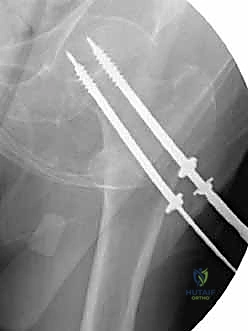

لماذا نستخدم 3 مسامير؟ (هندسة المثلث المقلوب)

يعتمد الأستاذ الدكتور محمد هطيف على مبادئ الميكانيكا الحيوية (Biomechanics) في التثبيت. يتم عادةً إدخال ثلاثة مسامير متوازية في عنق الفخذ. لا يتم وضعها بشكل عشوائي، بل تُرتب في شكل مثلث مقلوب (Inverted Triangle):

1. المسمار السفلي (Inferior Screw): يُوضع أولاً ليكون الدعامة الأساسية التي تستند على الكورتيكس السفلي الصلب لعنق الفخذ (Calcar)، وهو يتحمل أكبر قدر من وزن الجسم.

2. المسمار الأمامي العلوي (Antero-superior Screw).

3. المسمار الخلفي العلوي (Postero-superior Screw).

هذا التوزيع الثلاثي يوفر ثباتًا دورانيًا (Rotational Stability) ممتازًا ويمنع رأس الفخذ من الانزلاق أو الدوران حول محوره، كما يسمح بانضغاط الكسر (Compression) على طول خط الكسر، مما يحفز الخلايا العظمية على الالتئام السريع.